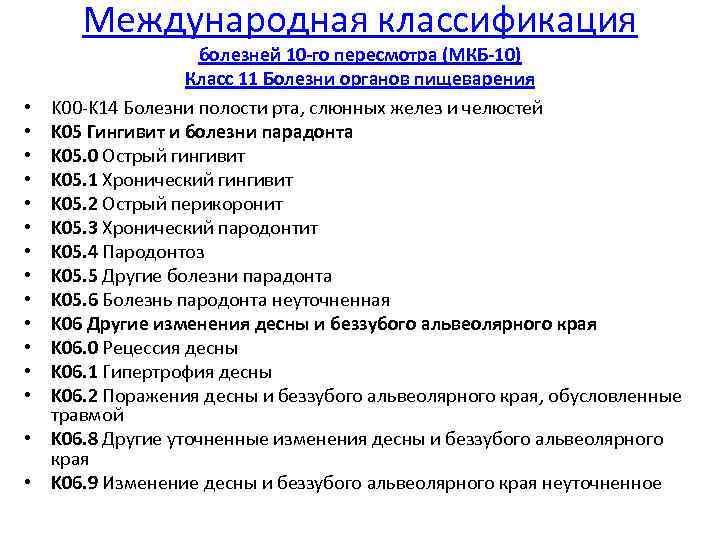

Код мкб 10 атерома головы

Код мкб 10 атерома головы 109 фото